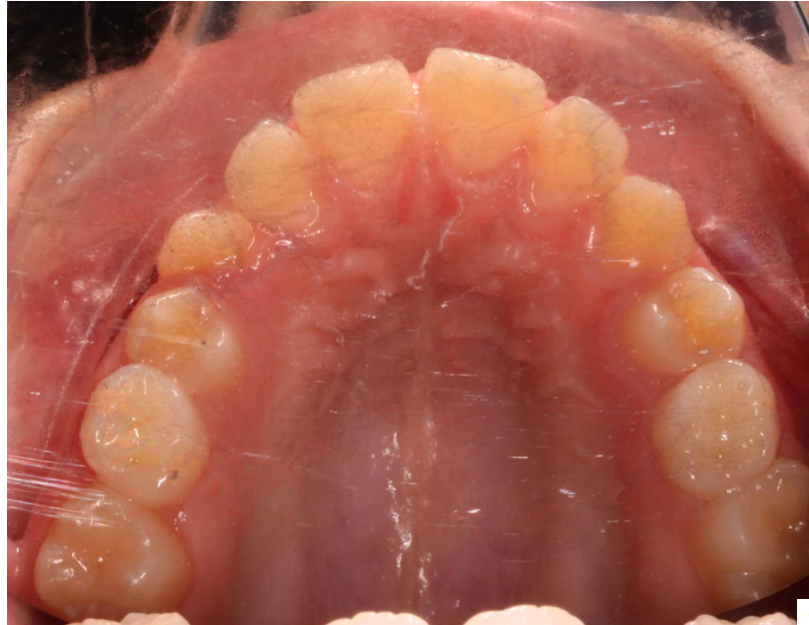

Llama la atención a primera vista la mordida abierta bilateral, especialmente pronunciada entre el cuadrante 1 y 4 debido a una interposición lingual en posición estática. Entre otros hallazgos fundamentales, observamos: un patrón dolicofacial severo (VERT: -2), una compresión de la arcada superior que cursa con un perfil y relación oclusal de clase III y la rotación del 35 y 45. Este caso se trató con un disyuntor, exodoncias de 44 y 34, brackets convencionales y educadores para rehabilitación de la lengua en un tiempo de 22 meses. Aunque estoy satisfecho con el resultado final, me hubiera gustado clavar la interscuspidación de premolares en el cuadrante I y IV, y mejorar la relación oclusal de cuadrante II y III. Sin embargo, lo bonito, es que hay a veces, en la ortodoncia real, que el paciente está satisfecho y quiere terminar antes de tiempo, o por el contrario, que el profesional intenta pero no consigue el resultado deseado. Y a mí más que compartir casos perfectos, me gusta mostrar mis errores, mi realidad.

La ilustración nos deja entrever algo tan fácil como que en un paladar pequeño no entra una lengua grande. Y viceversa, en un paladar grande entra una lengua grande. Llevándonos dicha explicación al caso que nos atañe, podemos ver  en la fotografía lateral del lado derecho como la lengua escapa y busca espacio, de manera permanente, entre el cuadrante 1 y 4,  estímulo que mantenido en el tiempo generó en una mordida abierta lateral.